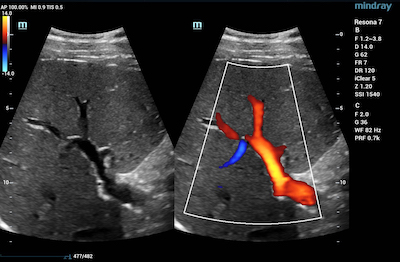

- Kidneys – CDI is used in renal ultrasonography to assess kidney issues such as renal hypertension, renal vein thrombosis, tumors, and hypovolemia – a condition that occurs from low blood volume.

Color Doppler Glazing Flow of Renal Color Doppler Ultra Micro Angiography of Artery and Vein

Color Doppler Ultra Micro Angiography of Renal Cortex Perfusion